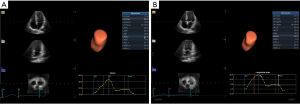

4D Auto LAQ analysis

Images were imported into the EchoPAC203 software (GE Healthcare) and selected for analysis. The analysis mode was entered, and the volume and 4D Auto LAQ sub-mode were sequentially selected. After that, the sampling point was placed in the middle of the mitral orifice in the 3 planes. The ‘review’ function was selected to obtain the LA parameters, including volume and strain parameters, measured by 4D Auto LAQ, (Figure 2 and Video 1).

Volume parameters were volume at onset of LA contraction (LA VpreA) and LAEF, while LAS parameters were longitudinal and circumferential strains. The reference point was set at the left ventricle ED. During the reservoir phase, the LA wall lengthened, so the strain in this phase had a positive value. In the other 2 phases, the LA wall shortened, so the strains in these phases had negative values. LA longitudinal strain parameters obtained using this technique included LA reservoir strain (LASr), LA conduit strain (LAScd), and LA contraction strain (LASct), and LA circumferential strain parameters obtained included LA reservoir circumferential strain (LASr-c), LA conduit circumferential strain (LAScd-c), and LA contraction circumferential strain (LASct-c).